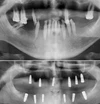

Implant tedavisi